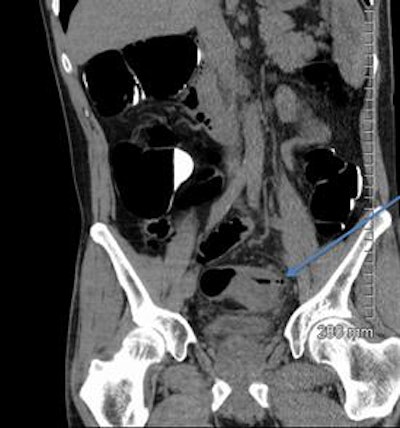

A 52-year-old man with a benign stricture, categorized as C4E1D4. The arrows highlight the smooth gradual transmural thickening within a diverticular laden sigmoid colon. Benign stricture was confirmed with surgical resection.

In terms of pathology within the D3 and D4 categories, 60 cases showed sigmoid diverticular disease on imaging, 10 showed sigmoid strictures, diverticular abscesses were found in five cases, and two cases included Crohn's or ulcerative colitis, they reported. Within the D3/D4 category, 24% underwent further intervention, either surgical (eight cases) or endoscopic (12 cases).